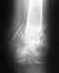

перипротезный перелом

слом фиксатора при недавнем протезировании тотальном тзобедренного сустава